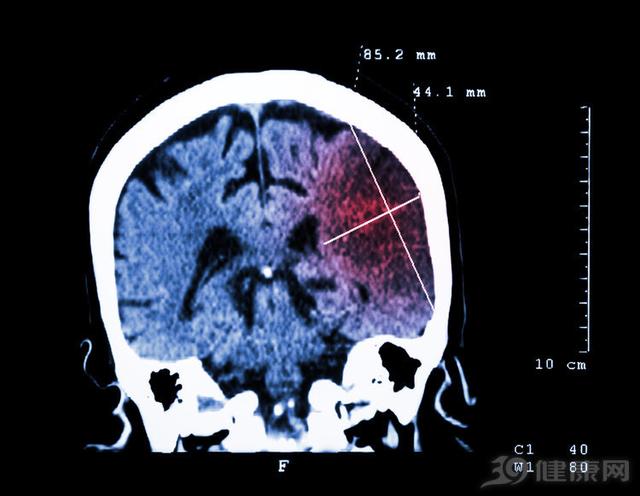

腦梗是一個再常見不過的病了,一般來說,只要發生可能危及生命。同時,它又跟其他的慢性病相關,如糖尿病、高血壓、心律失常等等。總而言之,預防腦梗,是延壽、保證健康的重要一環。

腦梗塞發生后,如果患者沒有採取正確的預防方法,有將近30%的患者在五年內會出現第二次腦梗死。主要原因是腦梗塞一旦發生,表明機體有血栓形成的基本因素,即血管內皮損傷、血液粘度變化、血流動力改變等。如果這些因素沒有得到有效的控制,腦梗塞將被重新激發,嚴重還可能導致複發性腦梗死。臨床證據表明,腦梗死複發的次數越多,預后越差,死亡率越高。因此,預防腦梗死顯得尤其重要。